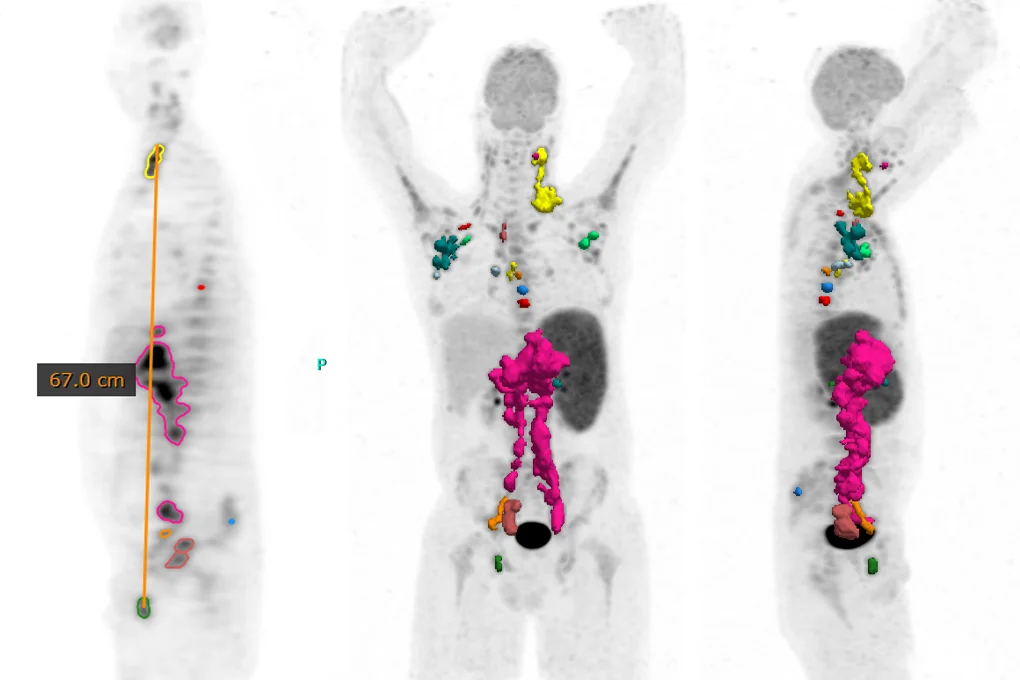

Advanced oncology tools

Quantify total metabolic tumor volume even in the most challenging cases with a versatile toolkit including single click lesion segmentation, thresholding, and splitting tools. Use the blob-splitter to help differentiate clinically relevant uptake from physiological or edit with a 3D paintbrush. Measure ‘DMax’* for disseminated disease to quantify spread. Flexible and intuitive, region drawing has never been so easy.

Hermia provides a powerful and intuitive toolkit for the display and analysis of nuclear medicine images. Supported data includes PET/CT, SPECT/CT, PET/MR, RTDOSE and 2D nuclear medicine images.

Data from a Siemens Biograph Vision Quadra Whole-Body PET/CT provided by Inselspital Bern, Switzerland